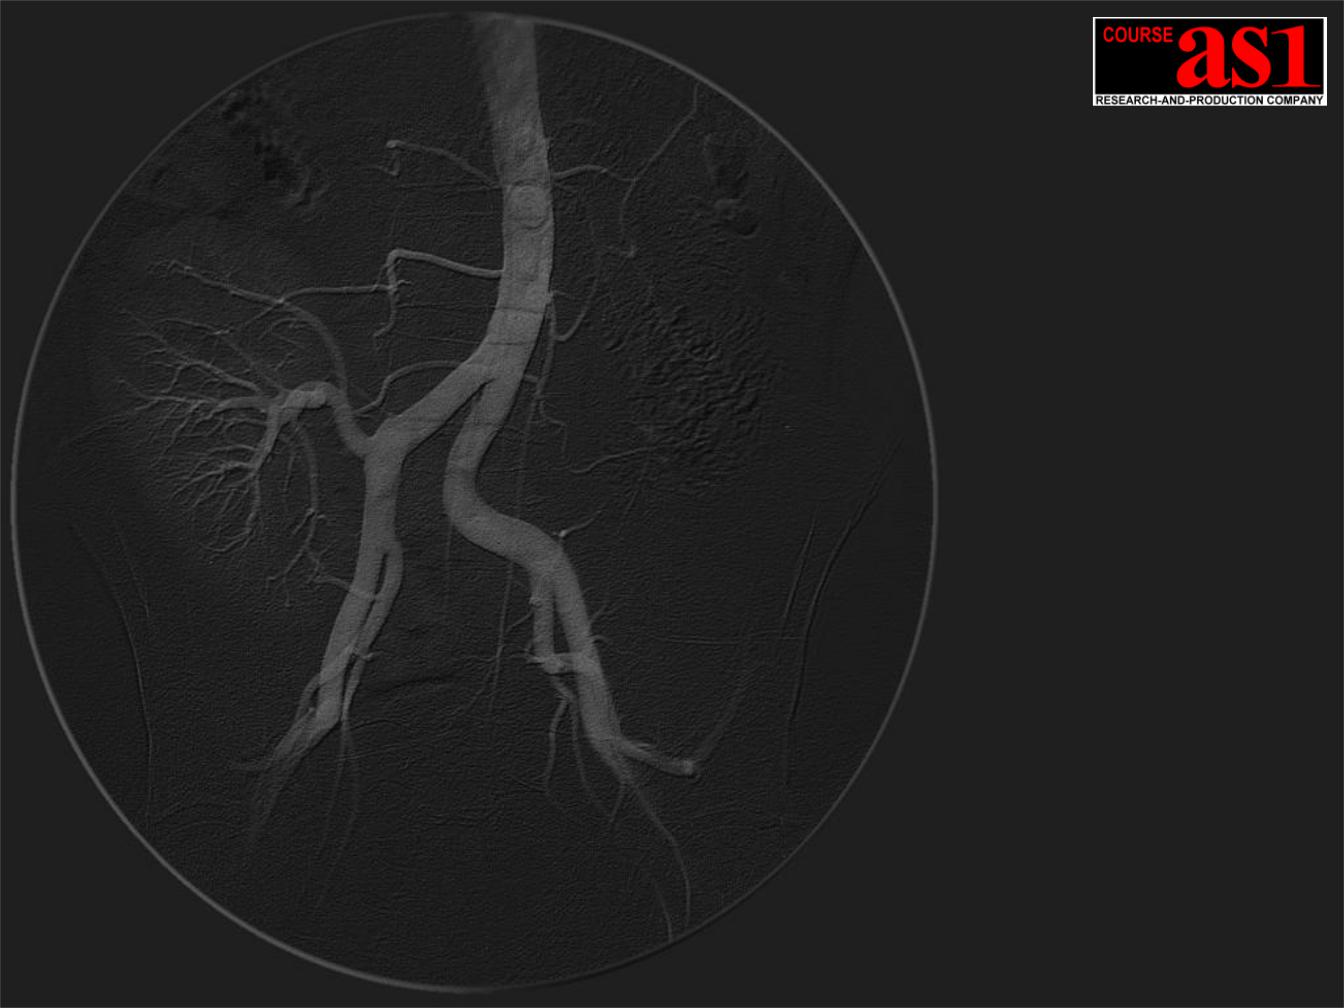

7.Аппаратная Мульти-модальность – рентгеновский экспертный ангиографический комплекс и рентгеновский компьютерный томограф сверхвысокого разрешения экспертного класса в едином конструктивном исполнении.